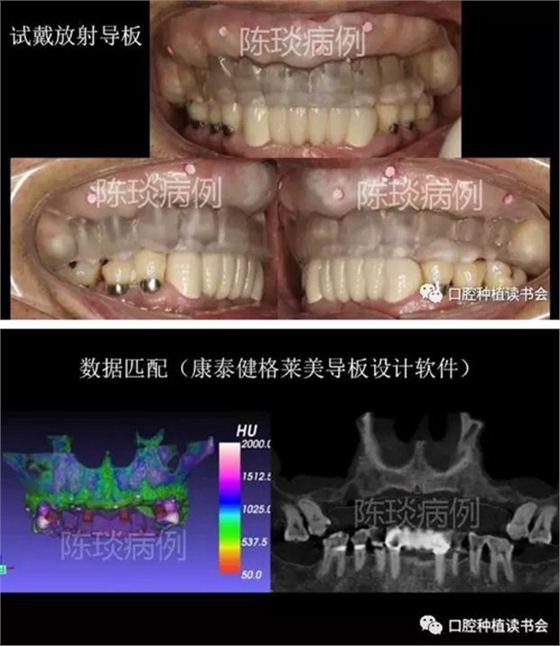

(1)制作臨時義齒以及放射導(dǎo)板,根據(jù)石膏模型設(shè)計放射導(dǎo)板,并確定顯影標記。

(2)佩戴放射導(dǎo)板拍CBCT后,設(shè)計數(shù)字種植導(dǎo)板。